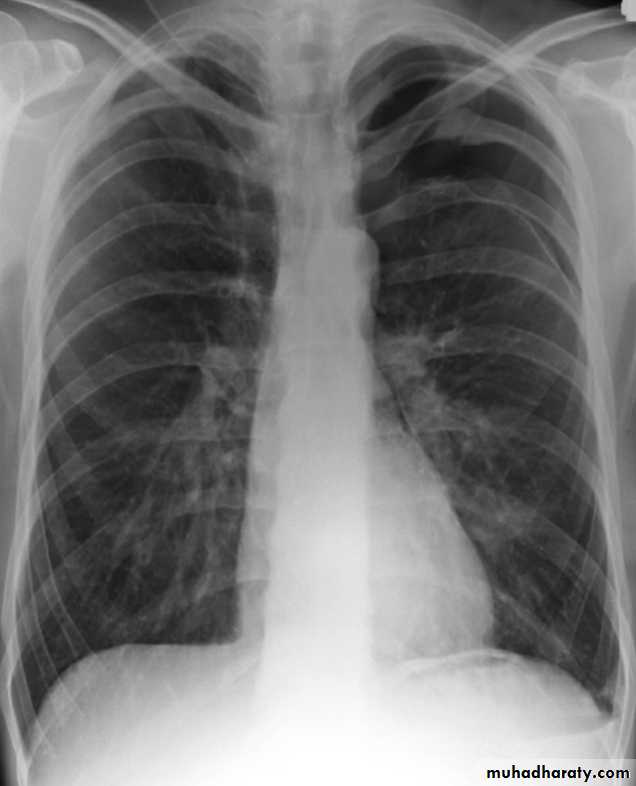

PneumothoraxPneumothorax refers to the presence of gas (air) in the pleural space. When this collection of gas is constantly enlarging with resulting compression of mediastinal structures it can be life-threatening and is known as a tension pneumothorax

A pneumothorax is, when looked for, usually relatively easily appreciated. Typically they demonstrate:

visible visceral pleural edge see as a very thin, sharp white line

no lung markings are seen peripheral to this line

the peripheral space is radiolucent compared to adjacent lung

the lung may completely collapse

the mediastinum should not shift away from the pneumothorax unless a tension pneumothorax is present